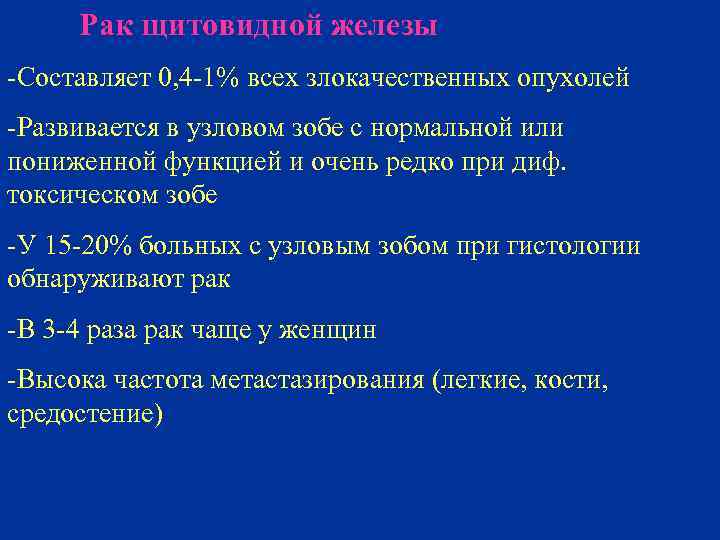

Рак щитовидной железы -Составляет 0, 4 -1% всех злокачественных опухолей -Развивается в узловом зобе с нормальной или пониженной функцией и очень редко при диф. токсическом зобе -У 15 -20% больных с узловым зобом при гистологии обнаруживают рак -В 3 -4 раза рак чаще у женщин -Высока частота метастазирования (легкие, кости, средостение)

Рак щитовидной железы -Составляет 0, 4 -1% всех злокачественных опухолей -Развивается в узловом зобе с нормальной или пониженной функцией и очень редко при диф. токсическом зобе -У 15 -20% больных с узловым зобом при гистологии обнаруживают рак -В 3 -4 раза рак чаще у женщин -Высока частота метастазирования (легкие, кости, средостение)